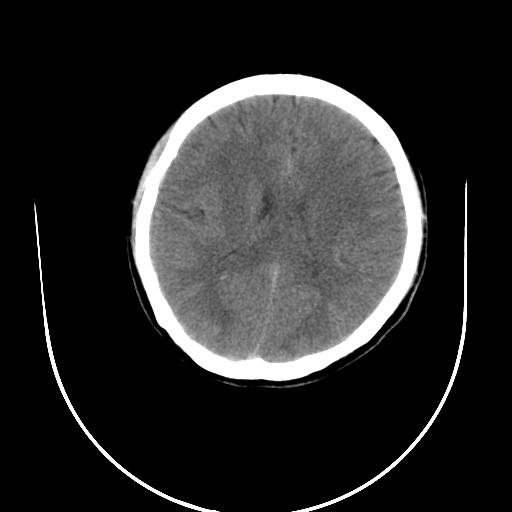

标题: CT10010:女/24岁,癫痫一周,发作时间不固定. [打印本页]

标题: CT10010:女/24岁,癫痫一周,发作时间不固定.

右侧额叶正常吗?

右额叶镰旁饱满.

右侧外侧沟?中央沟?可能有问题,不知以前有没有癫痫过,最好是增强下,排除局部血管畸形等病变

倒数第6幅图中线结构有点偏,而侧脑室额角未见异常,可结合增强扫描。